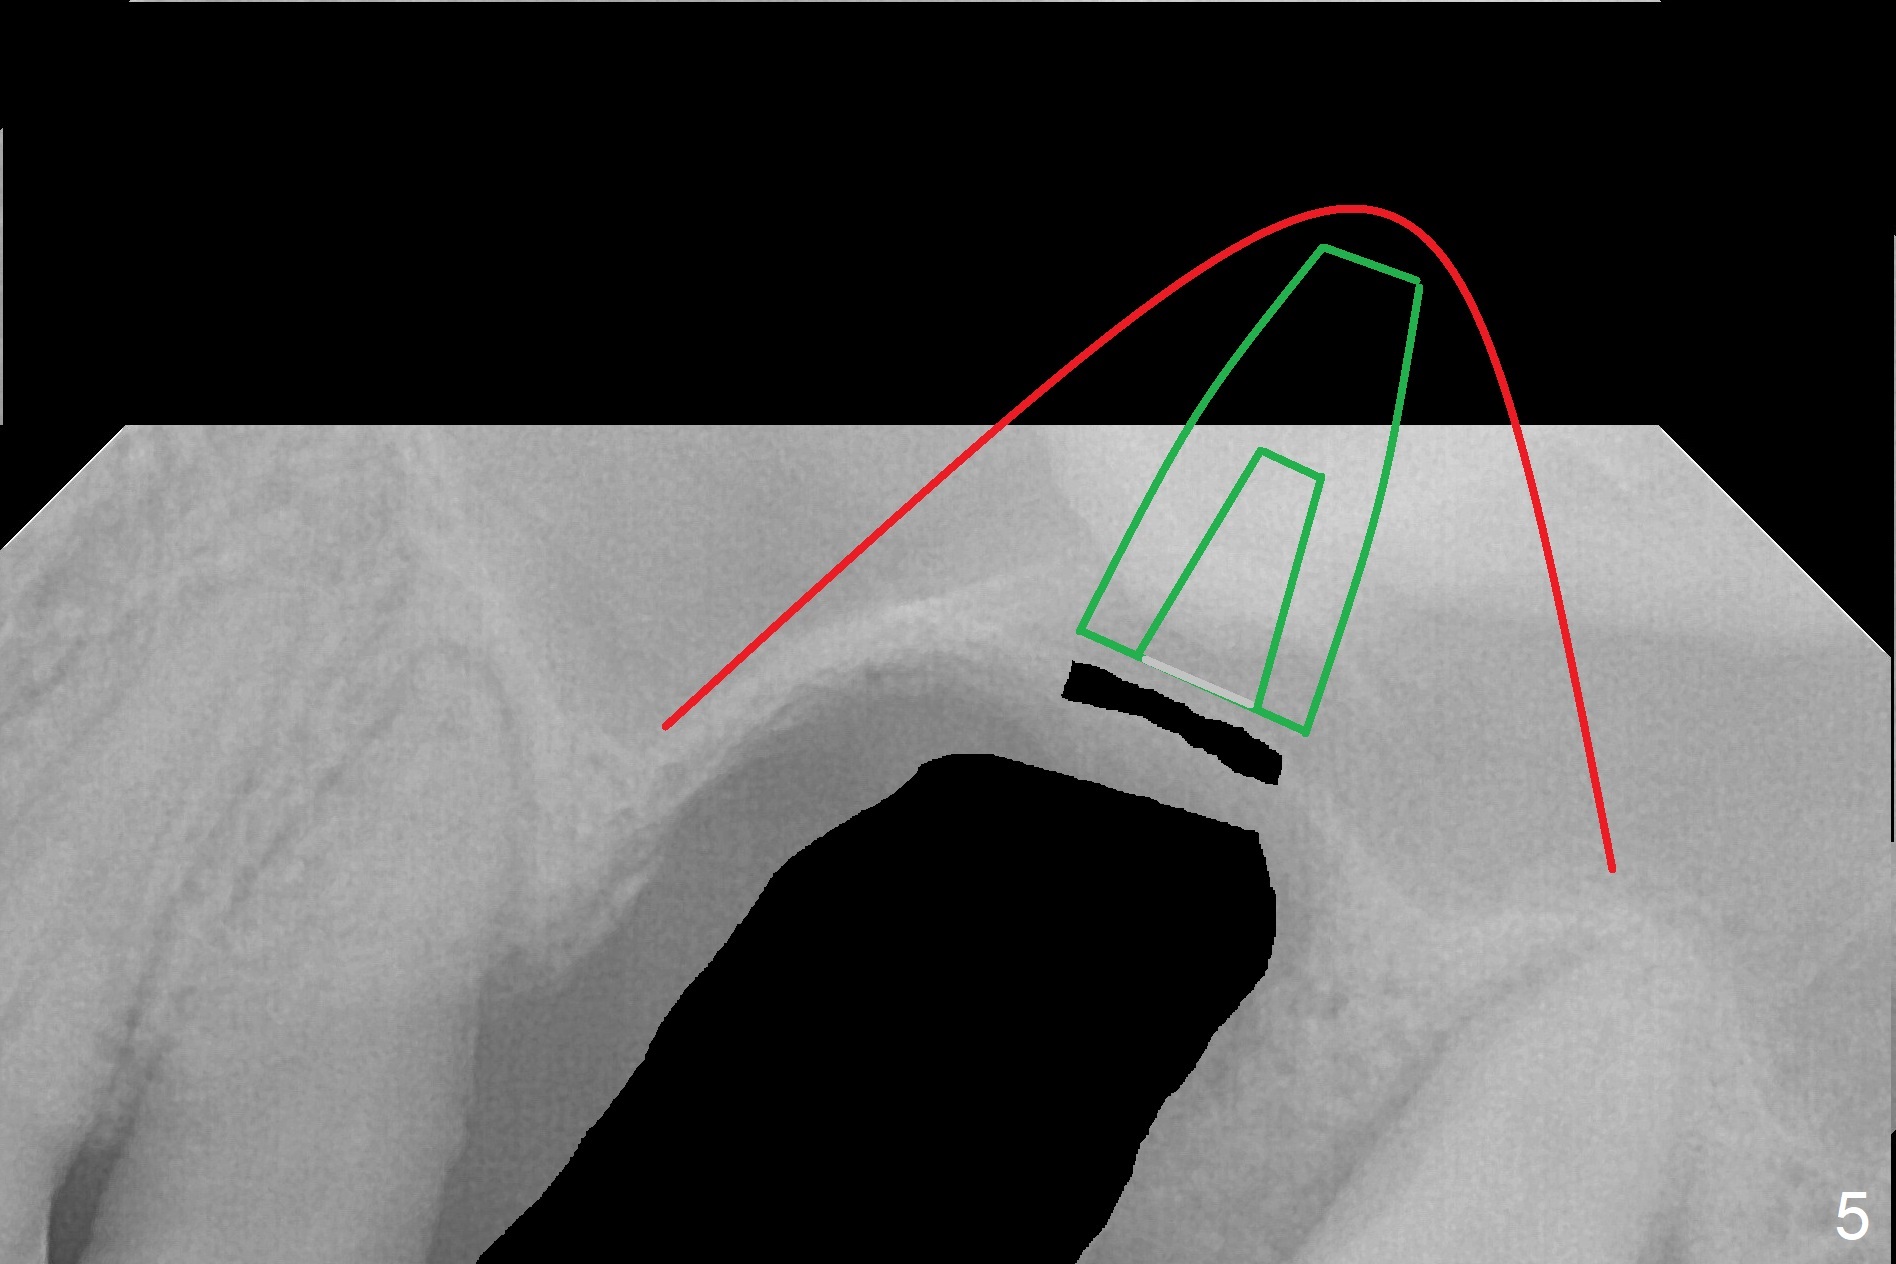

When the displaced tooth #14 (Fig.1) with palatal gingival recession (Fig.2) is extracted, the buccal plate is low, while the palatal one is lost.  Osteotomy is initiated in the bottom of the large socket with Marking Drill.  The bone turns bluish, suggesting thin bone (in fact less than 1 mm as well as low density).  Magic Sinus Lifter (Fig.3 *, Fig.4 blue area) is used for sinus lift (Fig.4 (red curved line: lifted sinus membrane; grey area: a portion of the lifted sinus floor), followed by insertion of a piece of PRF plug and Vanilla bone graft for sinus lift.  The osteotomy is enlarged lightly with 4.8 mm Magic Drill (compare black strips between Fig.4,5).  A 5x9 mm dummy implant (Fig.5 green) is dislodged into the sinus.  The lifted sinus membrane holds the implant in place.  The black thin strip in Fig.5 and black circle in Fig.6a (occlusal view) represents the osteotomy.  After increase in the osteotomy with Lindamann bur (Fig.6b red circle), the implant (Fig.6c green) is retrieved with endodontic forceps (Fig.6c two blue dots (beaks of the forceps); Fig.7,8).  With the enlarged osteotomy (Fig.6d), a 6x9 mm dummy implant is placed deep (Fig.9).  The definitive implant is 6.5x11 mm with insertion torque ~ 15 Ncm (Fig.10).  With placement of a healing screw and further placement of allograft (Fig.11 *), the socket is closed with PRF membrane and collagen plug (Fig.12).